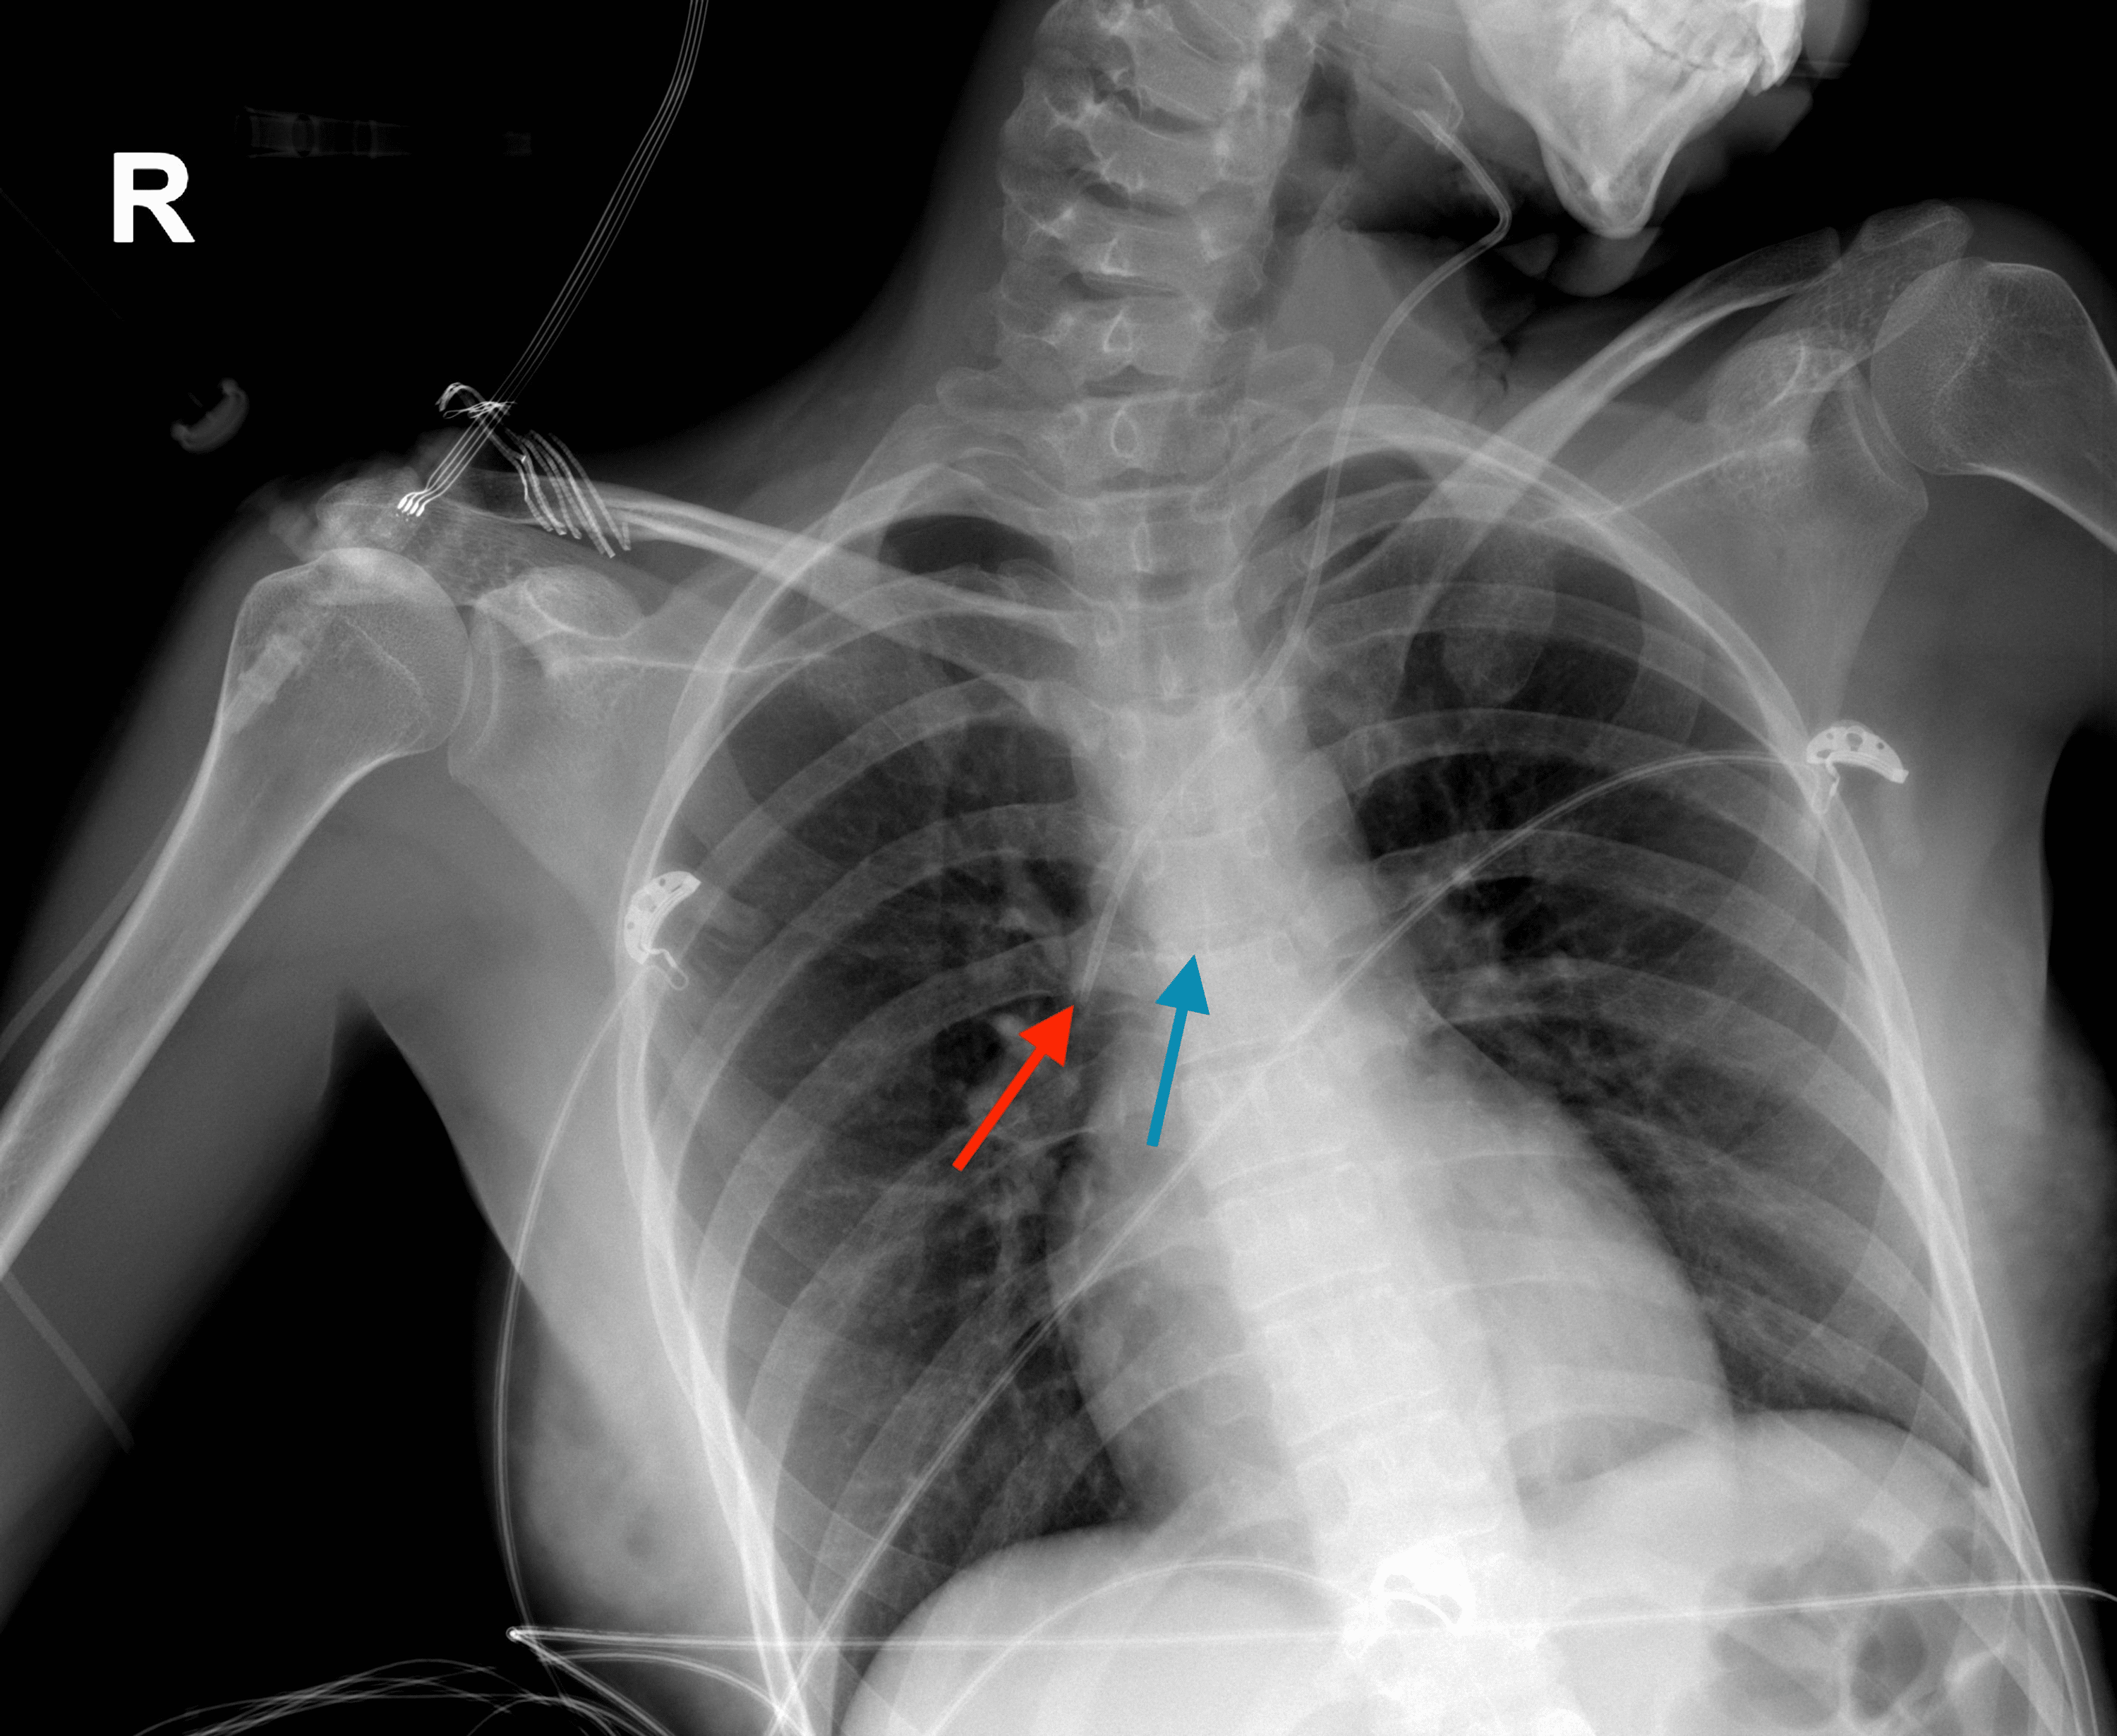

From www.dreamstime.com

Xray Placement Right Internal Jugular Catheter Stock Photo Image of Jugular Vein Catheter Placement Cpt Code The approach to central venous catheter placement can be peripherally inserted, subclavian vein, or internal jugular vein. A guidewire was passed under. According to cpt®, “to qualify as a central venous catheter or device, the tip of the. This site was abandoned and using ultrasound guidance, the right internal jugular vein was punctured. Using this method for central venous access. Jugular Vein Catheter Placement Cpt Code.